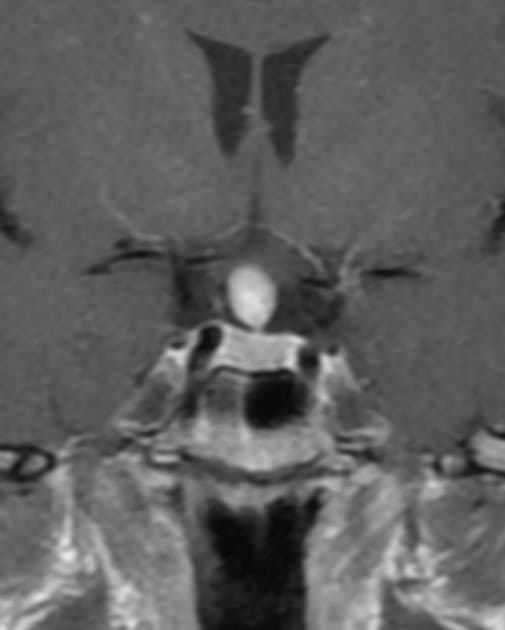

Coronal T2

Chụp MRI sọ não phát hiện khối tổn thương dạng đặc, nhiều thùy (multilobulated, solid) nằm ở phần trước của não thất ba (third ventricle).

Khối tổn thương có tín hiệu đồng tín hiệu (isointense) trên hình ảnh T1W, tăng tín hiệu không đồng nhất (heterogenous hyperintense) trên hình ảnh T2W, không có hạn chế khuếch tán (no diffusion restriction), với một số vùng nhỏ có giá trị ADC thấp. Sau tiêm thuốc tương phản, khối cho thấy tăng quang mạnh (vivid enhancement) và đồng nhất (homogenous enhancement).

Về vị trí, hình ảnh tuyến yên (pituitary gland) và ngách trên thị (supraoptic recess) còn nguyên vẹn (intact) – thấy rõ nhất trên hình T1W – cho thấy khối không xuất phát từ vùng yên (sellar) hay vùng trên yên (suprasellar). Thay vào đó, khối làm cong xuống phía dưới sàn não thất ba và cuống yên (infundibulum), do đó khối nằm trong não thất ba (3rd ventricle).